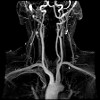

MRI of the neck arteries.

Магнитный резонанс артерий шеи (МР ангиография). Метод визуальной диагностики артериальных сосудов, которые снабжают мозг, а также состояния кровотока в них. Это выполняется путем облучения пациента радиоволнами в сильном магнитном поле томографа. Это может быть без контраста и контраста. Кровоснабжение мозга обеспечивается брахиоцефальным стволом, правой и левой подключичной артериями, правой и левой позвоночными артериями, общими правой и левой сонной артериями, внешней и внутренней сонной артерией - это сосудистые структуры, которые проходят через шея и являются предметом исследования для МР-ангиографии. В ходе исследования выявляются атеросклеротические изменения сосудистой стенки, сдавление сосудов позвонками или опухолью, аневризма и извилистость артерий, нарушения анатомического строения и многие другие. МР-ангиография артерий шеи необходима для планирования сосудистых операций (ангиопластика, протезирование ) И контроля их эффективности.